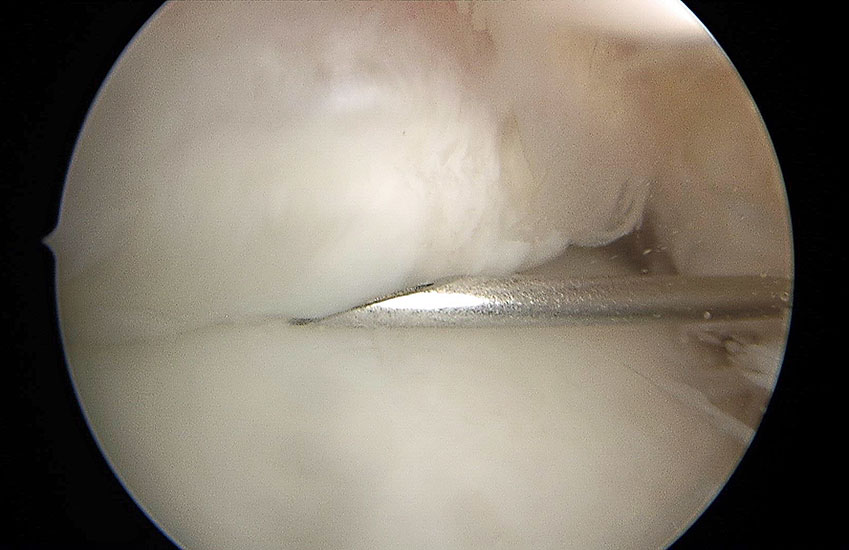

Abbildung 9, Video 4

Posttraumatische Arthrofibrose nach bimalleolärer OSG-Fraktur. Die ausgeprägten Verwachsungen (*) erschweren den Zugang zum Gelenk. Oftmals sind die intraartikulären Strukturen und der Gelenkspalt nach dem Einführen des Arthroskops nicht abgrenzbar, so dass zunächst eine Resektion der Narbenstränge mit einem Weichteilshaver erforderlich ist.